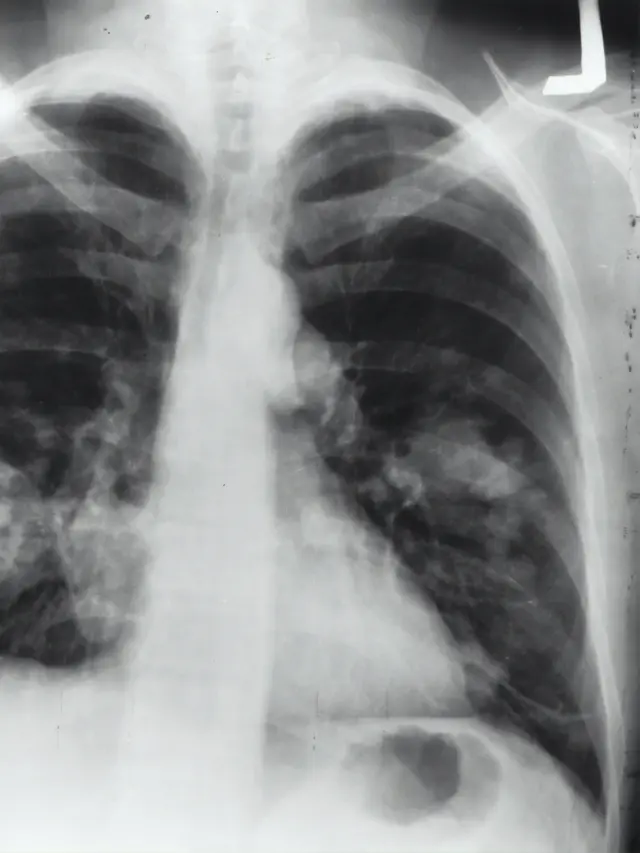

Dr. Jamal Zaini mengatakan skrining rutin sedini mungkin guna mendeteksi kanker paru pada tahap awal. Salah satu metode skrining yang direkomendasikan adalah Low-Dose Computed Tomography (LDCT), yang dapat membantu menurunkan angka kematian akibat kanker paru, terutama padakelompok berisiko tinggi.

"LDCT mampu mendeteksi kelainan pada paru sejak dini dan dalamukuran sangat kecil, bahkan sebelum munculnya gejala, sehingga memungkinkan intervensi lebih cepat dan peluang kesembuhan lebih besar,” lanjut dr.Jamal.

Dua studi besar mendukung efektivitas LDCT: National Lung Screening Trial (NLST) di Amerika Serikat mencatat penurunan kematian sebesar 20% dibanding rontgen dada biasa,sementara NELSON Trial di Eropa mencatat penurunan hingga 24% pada pria dan 33% pada wanita dalam periode 10 tahun dengan skrining tahunan.

Berdasarkan pedoman dari Kementerian Kesehatan Republik Indonesia, skrining menggunakan LDCT dianjurkan setiap dua tahun bagi individu berusia 45 tahun ke atas yang memiliki riwayat merokok berat, baik yang masih merokok maupun yang telah berhenti dalam 10 tahun terakhir, perokok pasif serta mereka yang memiliki riwayat pajanan karsinogenik. Bagi individu dengan riwayat genetik kanker dalam keluarga, skrining disarankan dimulai lebih awal, yaitu pada usia 40 tahun.

Sahabat Fimela, pemeriksaan kesehatan rutin sangat penting, terutama bagi perokok atau mereka yang terpapar zat karsinogenik. Deteksi dini meningkatkan peluang kesembuhan. Skrining kanker paru-paru, seperti CT scan low-dose, dapat direkomendasikan untuk kelompok berisiko tinggi.